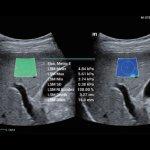

با توجه به اینکه دستگاه های جدید بررسی فیبروز کبد (سفتی کبد)بر پایه سونوگرافی میباشد،در مرکز تخصصی فیرواسکن دکتر شماعی ،فیبرواسکن کبد صرفا توسط پزشک متخصص رادیولوژی انجام میشود و علاوه بر انجام فیبرواسکن و ارزیابی فیبروز( سفتی ) کبد و تعیین میزان کبد چرب، سونوگرافی کبد و بررسی کیسه صفرا و مجاری صفراوی نیز بدون دریافت هزینه انجام خواهد شد

مرکز تخصصی فیبرواسکن دکتر شماعی جز محدود مراکزی در مشهد میباشد که انجام فیبرو اسکن با استفاده از جدید ترین دستگاه ها انجام میگرد و تمامی مراحل انجام فیبرواسکن و تجزیه و تحلیل اطلاعات و گزارش فیبرواسکن توسط پزشک متخصص صورت میگیرد.

با توجه به اینکه نتایج فیبرواسکن کبد نقش تعیین کننده در درمان کبد چرب دارد،لذا این مرکز متعهد به انجام فیبرواسکن کبد توسط پزشک متخصص و با صرف وقت لازم میباشد